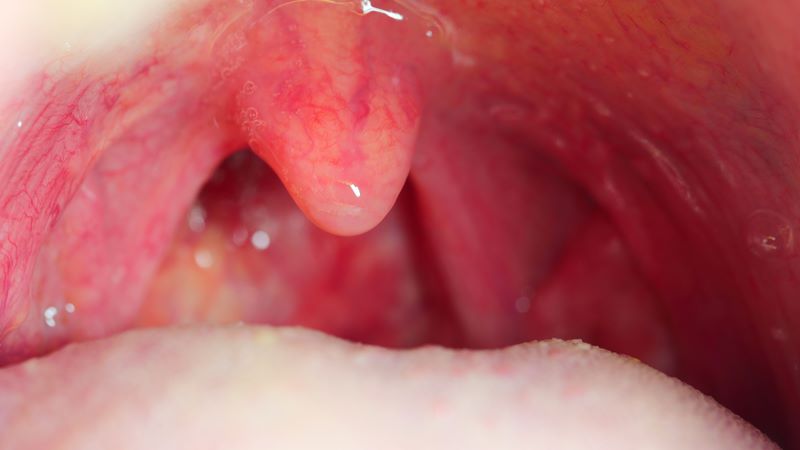

Có nên cắt amidan cho người lớn không?

Vấn đề “có nên cắt amidan cho người lớn không?” phụ thuộc hoàn toàn vào chỉ định y khoa. Không phải mọi trường hợp viêm amidan ở người lớn đều cần phẫu thuật. Khi đã có chỉ định rõ ràng, người lớn có nên cắt amidan để cải thiện sức khỏe và chất lượng cuộc sống.

“Khi nào nên cắt amidan cho người lớn?” – Câu trả lời là trong trường hợp:

- Viêm amidan tái phát nhiều lần trong năm: Nếu bạn thường xuyên bị viêm amidan ảnh hưởng đến sinh hoạt, công việc hoặc chất lượng cuộc sống thì nên cân nhắc phẫu thuật.

- Amidan hoặc VA quá phát: Khi amidan và VA phát triển quá mức, gây chèn ép đường thở, ngủ ngáy hoặc ngưng thở khi ngủ, việc cắt amidan là cần thiết để đảm bảo hô hấp và giấc ngủ.

- Tổn thương dạng áp xe quanh amidan: Sau các đợt viêm cấp, nếu xuất hiện nguy cơ tái phát hoặc biến chứng, bác sĩ sẽ khuyến nghị phẫu thuật nhằm phòng ngừa.

- Các chỉ định phụ khác: Bao gồm sỏi amidan, hơi thở hôi… những trường hợp này sẽ được cân nhắc dựa trên tình trạng cụ thể của từng bệnh nhân.

Hiện nay, gần như 100% các ca cắt amidan được thực hiện dưới gây mê, giúp quá trình phẫu thuật nhẹ nhàng, kiểm soát hốc mổ tốt và giảm cảm giác đau cho bệnh nhân. Khi có chỉ định rõ ràng về viêm tái phát, quá phát hoặc biến chứng thì việc cắt amidan là cần thiết. Việc thực hiện đúng thời điểm sẽ giúp cải thiện sức khỏe, giấc ngủ và chất lượng cuộc sống.